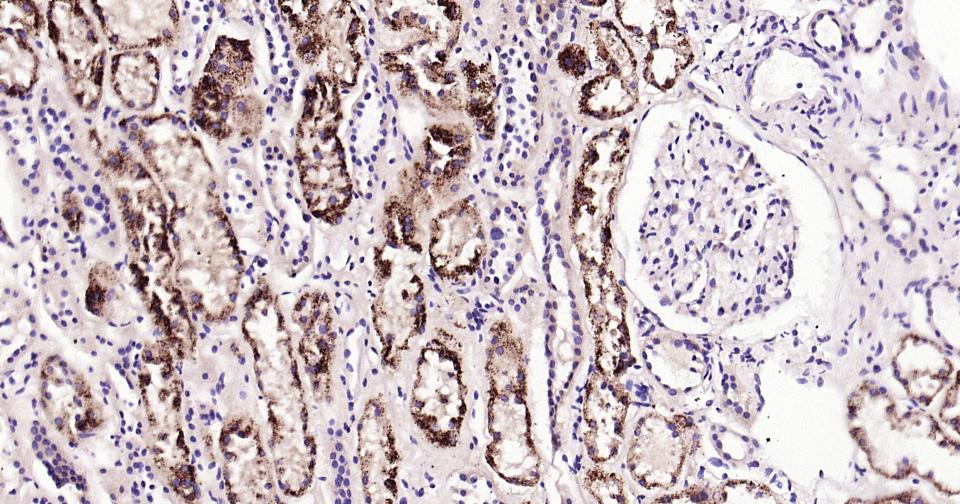

| IHC-P | Human, Mouse, Rat | 1:100-500 | |